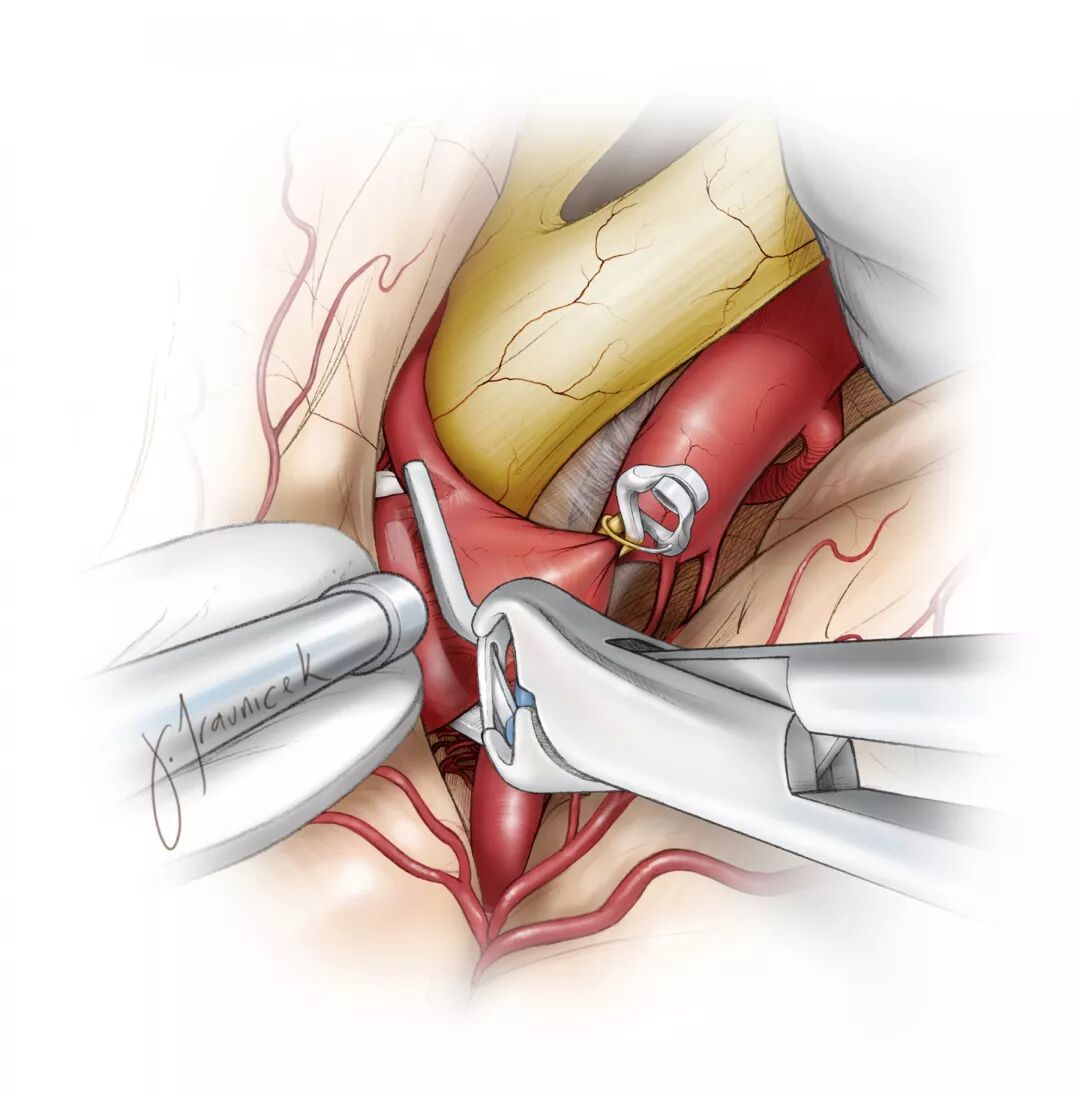

图1:作为夹闭大型后交通动脉动脉瘤(左)时,逆向吸引减压技术的一部分,临时阻断载瘤动脉远端。动脉瘤显著减压后有利于安全和有效地放置永久动脉瘤夹(右)。

图8:在行逆向吸引减压技术夹闭大型后交通动脉动脉瘤时,临时阻断载瘤动脉远端血供。以两枚直角开窗夹将动脉瘤夹闭(内嵌图)。在行逆向吸引减压技术时,于颈部颈内动脉放置球囊导管作临时阻断用。充盈球囊,临时夹在动脉瘤远端阻断颈内动脉,然后通过血管内导管对动脉瘤抽吸减压。